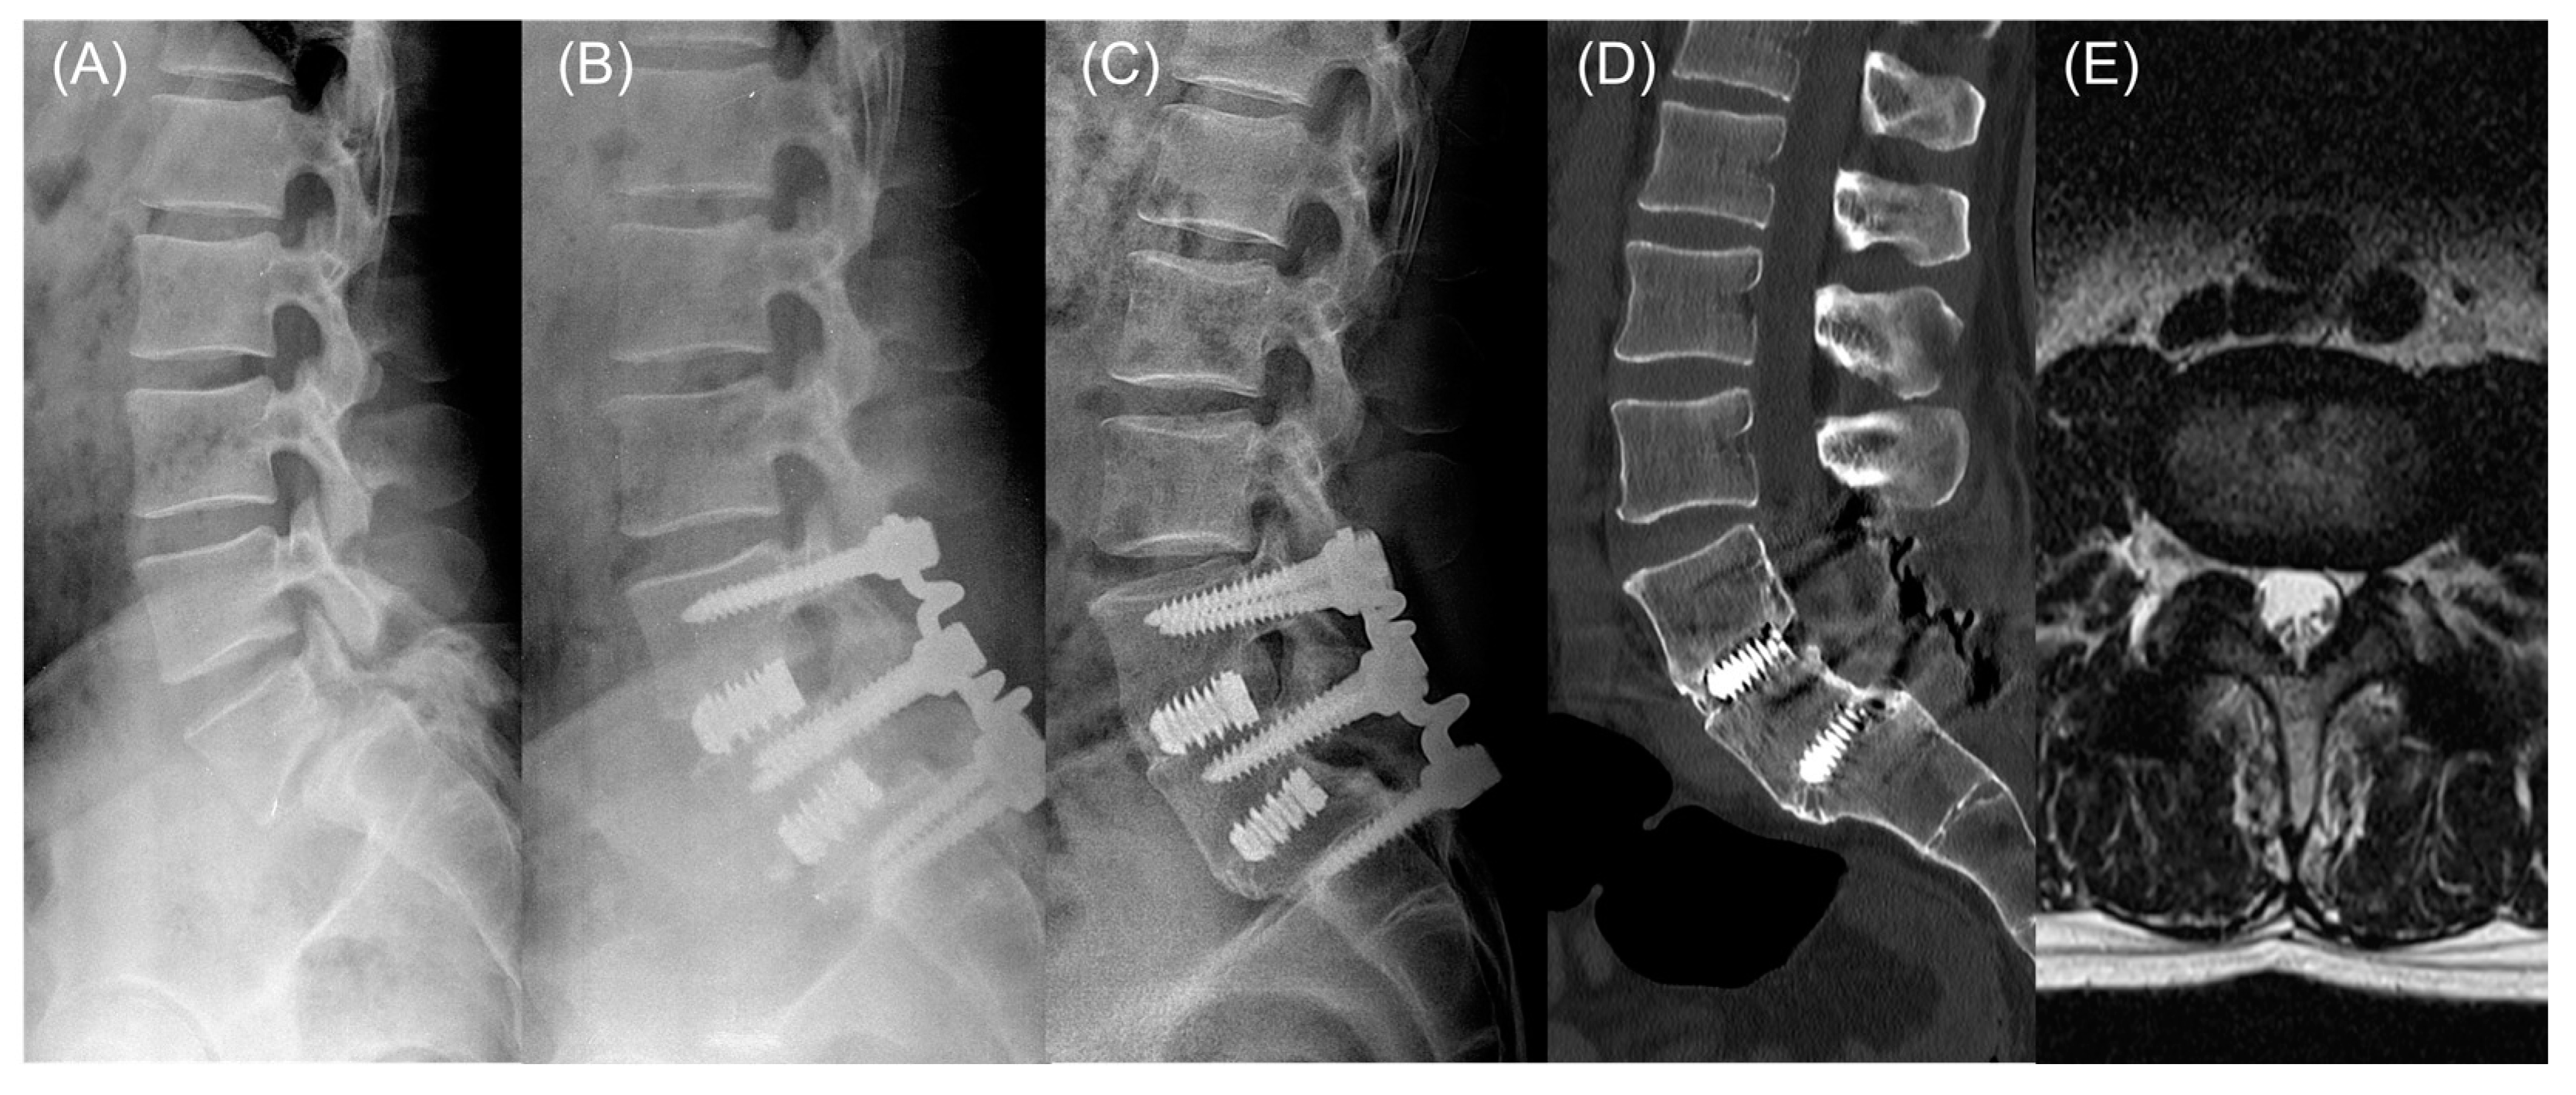

- Kim, Y.-S.; Zhang, H.-Y.; Moon, B.-J.; Park, K.-W.; Ji, K.-Y.; Lee, W.-C.; Oh, K.-S.; Ryu, G.-U.; Kim, D.H. Nitinol Spring Rod Dynamic Stabilization System and Nitinol Memory Loops in Surgical Treatment for Lumbar Disc Disorders: Short-Term Follow Up. Neurosurg. Focus. 2007, 22, 1–9. [Google Scholar] [CrossRef]